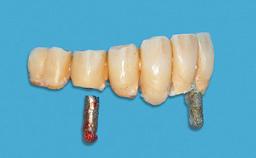

An 83-year-old man presented together with his caregiver at the dental department of the Medical University of Innsbruck, Austria with complaints of swelling in the right maxillary canine area and loss of retention of his 5-years-old mandibular denture. The patient had a significant medical history (20 years) of bipolar affective disorder with moderate depression (F 31.3) and dementia in Alzheimer’s disease (F 00.2). The patient had been in ambulant psychiatric therapy for his depressive illness for the past 20 years. He lived alone and had no children; his sister assisted with daily living. She reported that the patient exhibited compulsive hoarding behavior. In the previous two months, she had noted increasing disorientation and vertigo in the patient. She therefore accompanied him for a medical consultation at the Department of Psychiatry and Psychotherapy of the Medical University of Innsbruck. He was released home after a 6-week inpatient stay.